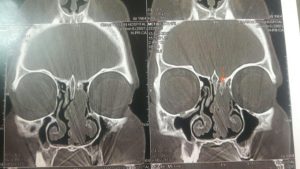

2. سی تی اسکن

تشخیص به وسیله این روش تصویربرداری دقیق تر از سایر روشها می باشد زیرا میزان درگیری استخوان از این طریق نشان می دهد. همچنین برای تشخیص تومور در اطراف مغز از این روش استفاده می شود.

این عکس ها متعلق به خانمی ۵۲ ساله با سابقه گرفتگی بینی از چند سال قبل و نیز سابقه جراحی پولیپ در ۱۰ سال گذشته می باشد در بررسی بالینی نکته دیگری جز توده ای به ظاهر پولیپ مانند در بینی نبود. محل کلی تومور با خط مشکی مشخص شده است

فلش نارنجی محل منشا تومور درنازکترین استخوان حدفاصل بینی ومغز را نشان می دهد.

که در تصویر برداری با سی تی اسکن بینی و سینوس نمای موجود شک به این نوع پاپیلوم را برمی انگیخت که طی عمل جراحی اندوسکوپیک و کمک مداوم سر جراحی از همکاران پاتولوژیست وجود این توده ثابت گردیید. و متاسفانه محل پیدایش و منشا اولیه آن در قاعده جمجمه و در محل نازک ترین قسمت استخوان بین بینی و سینوس ها و مغز به طور عملی محرز گردید و این نایحه به طور کامل با کمک ابزارهای خاص تراشیده شده و عمل با اطمینان از برداشت کامل بدون آسیب و صدمه به عناصر حیاتی نظیر مز خاتمه پیدا کرد.